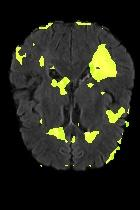

Current unsupervised anomaly localization approaches rely on generative models to learn the distribution of normal images, which is later used to identify potential anomalous regions derived from errors on the reconstructed images. However, a main limitation of nearly all prior literature is the need of employing anomalous images to set a class-specific threshold to locate the anomalies. This limits their usability in realistic scenarios, where only normal data is typically accessible. Despite this major drawback, only a handful of works have addressed this limitation, by integrating supervision on attention maps during training. In this work, we propose a novel formulation that does not require accessing images with abnormalities to define the threshold. Furthermore, and in contrast to very recent work, the proposed constraint is formulated in a more principled manner, leveraging well-known knowledge in constrained optimization. In particular, the equality constraint on the attention maps in prior work is replaced by an inequality constraint, which allows more flexibility. In addition, to address the limitations of penalty-based functions we employ an extension of the popular log-barrier methods to handle the constraint. Comprehensive experiments on the popular BRATS'19 dataset demonstrate that the proposed approach substantially outperforms relevant literature, establishing new state-of-the-art results for unsupervised lesion segmentation.